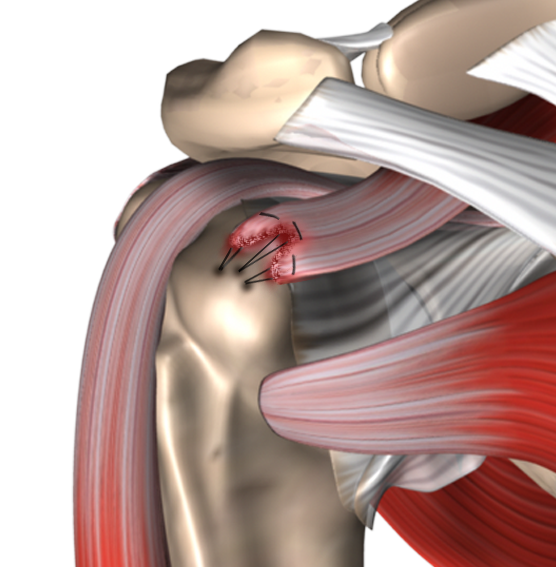

Фотографии мышц ротаторной манжеты плеча